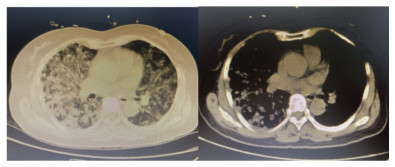

患者,女,64岁,居住农村,既往有糖耐量异常5年,未正规治疗,4年前诊断为“原发性甲状腺功能亢进”,经治疗已好转。无高风险、中风险地区旅居史,无境外旅居史,无新冠病毒肺炎确诊或疑似患者接触史。2020年7月31日患者无明显诱因下在家中出现发热,体温最高39.4 ℃,伴畏寒、全身乏力,无胸闷、胸痛,无咳嗽、咳痰,无腹痛、腹泻,无黑矇、晕厥,遂在家中自服“退热药”后体温降至正常,但体温仍有反复。8月2日早晨患者再次出现发热,伴畏寒、寒战,遂至本院发热门诊就诊,予查C-反应蛋白156 mg/L,降钙素原0.64 ng/L,考虑感染性发热,遂予“哌拉西林他唑巴坦钠4.5 g每12 h一次”静滴抗感染治疗,后患者突发呼吸费力,伴咳嗽、咯血,为鲜红色血液,量较多,遂于8月2日14:18送达本院急诊抢救室。来时患者呼吸急促,有咳嗽伴咳血性痰,双侧小腿持续性钝痛,查体:血压188/86 mmHg(1 mmHg=0.133 kPa),心率168次/min,呼吸36次/min,血氧饱和度50%,体温38.6 ℃。神志清,精神软,急性面容,双侧结膜略充血,全身皮肤黏膜未见明显充血、淤血,未触及淋巴结肿大。口唇微绀,两肺呼吸音粗,可闻及明显湿性啰音,心律齐,无明显病理性杂音;腹平软,无压痛反跳痛,四肢肌力Ⅴ级,两侧病理征未引出。予心电监护、特级护理、面罩吸氧、建立静脉通道,送检血常规、生化、血气、心肌酶、凝血酶原时间系列、痰培养等常规检查,同时予送检血标本行高通量测序,完善胸部CT检查(图 1)。辅助检查结果如下:8月2日胸腹部CT示两肺感染,腹部未见明显异常。血常规:白细胞计数7.9×109/L,中性粒细胞百分比89%,血红蛋白121 g/L,血小板计数104×109/L,C-反应蛋白156.82 mg/L。血生化:丙氨酸氨基转移酶51 U/L,天门冬氨酸氨基转移酶63 U/L,白蛋白34.5 g/L,总胆红素17.4 mmol/L,肌酐74 mol/L。心肌酶谱:心肌肌钙蛋白I 0.014 ng/mL,肌红蛋白322 ng/mL,肌酸激酶同工酶3.2 ng/mL。血气分析:pH 7.435,二氧化碳分压29 mmHg,氧分压53.5 mmHg,K+ 2.6 mmol/L,Na+ 132 mmol/L,血乳酸3.1 mmol/L。新型冠状病毒抗体、核酸阴性。接诊医师初步诊断为“咯血待查:疑似肺部感染,呼吸衰竭”,治疗上予亚胺培南0.5 g静滴经验性抗感染、甲泼尼龙80 mg静滴抗炎,同时予化痰、平喘等对症、支持。17:00患者出现呼吸费力加重,10 L/min面罩吸氧下血氧饱和度仍为70%,故予紧急气管插管、机械通气,随后转入ICU,联系感染科医师会诊,结合患者病史及CT影像学表现的广泛、片状密度增高影特点,考虑钩端螺旋体病可能性大,不排除“赫氏反应”,故继续予亚胺培南0.5 g静滴每6 h一次抗感染、甲泼尼龙80 mg静滴每12 h一次抗炎、白蛋白营养支持等治疗。8月3日更改甲泼尼龙80 mg静滴每天一次。8月4日高通基因测序回报:检测出问号钩端螺旋体DNA,符合入院时推断,明确病原体后予修正诊断为肺出血型钩体病伴赫氏反应。8月5日停亚胺培南,改青霉素160万单位静滴每8 h一次。8月8日患者病情稳定,拔除气管导管,予甲泼尼龙减量为40 mg静滴1次/d,8月9日复查胸部CT提示两肺斑片状、片状密度增高影较前有所吸收(图 2),停用甲泼尼龙。8月10日转入呼吸科。8月17日复查胸部CT提示两肺斑片状、片状、条索状密度增高影,较前明显吸收(图 3)。8月20日患者好转出院。9月18日随访,复查CT提示两肺散在条索状密度增高影,基本恢复正常(图 4)。

图 2 8月9日胸部CT示两肺斑片状、片状密度增高影较前有所吸收